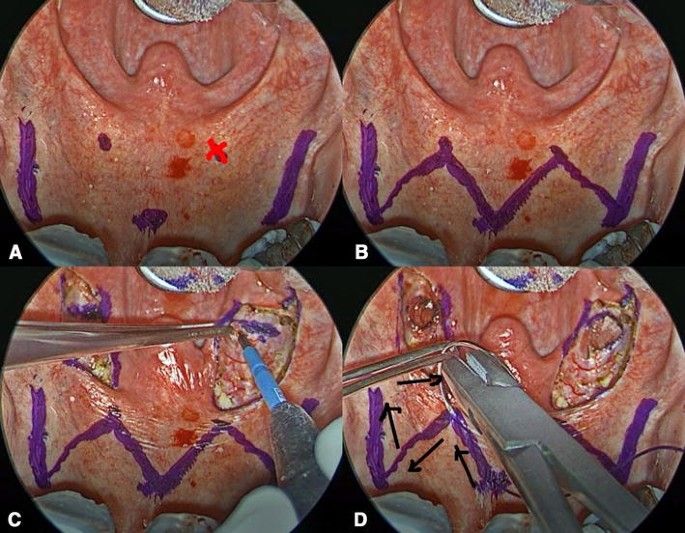

7. Pembedahan masalah tidur (Sleep Surgery)

Jika terapi CPAP atau cara rawatan konservatif lain tidak berkesan, pembedahan merupakan salah satu pilihan yang boleh diberikan untuk masalah dengkur. Prosedur seperti uvulopalatopharyngoplasty (UPPP) atau barbed reposition pharyngoplasty dapat mengurangkan penyempitan ruang pernafasan disebabkan oleh tisu tekak berlebihan, sekaligus menambahbaik pernafasan anda ketika tidur.